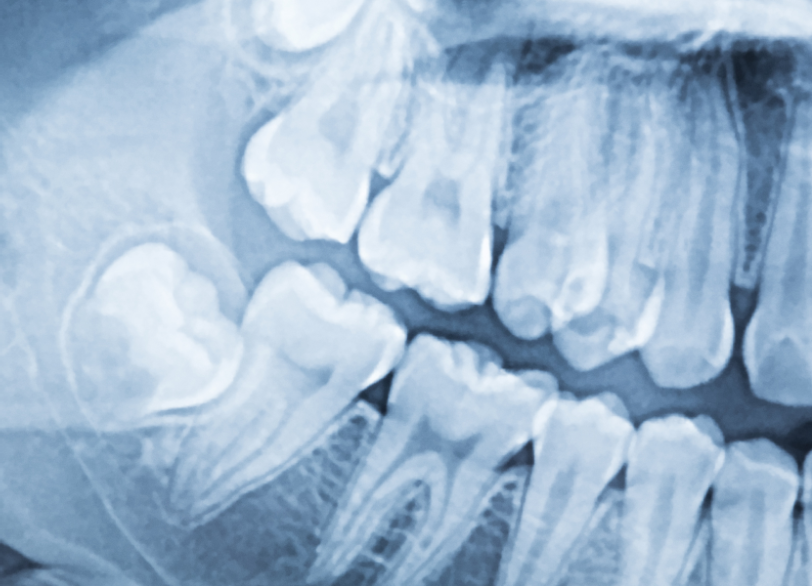

下の親知らずの根の近くには「下顎管(かがくかん)」という、下唇周囲の感覚を司る太い神経や血管が通っている管が存在します。 従来の二次元的なレントゲン写真では、この神経と親知らずの根が実際に接触しているのか、あるいは前後にずれているのかを正確に判断することは困難でした。 当院では親知らずの抜歯、特に神経との距離が近い難症例が疑われる場合には必ず事前に歯科用CTによる撮影を行います。

CTを用いることで、歯の根の形、骨の硬さ、そして何よりも神経や血管との三次元的な位置関係をミリ単位で正確に把握することができます。 この手術前の「見える化」こそが、神経麻痺などの偶発症のリスクを限りなくゼロに近づけ安全で確実な抜歯を行うための絶対的な条件であると私たちは考えています。